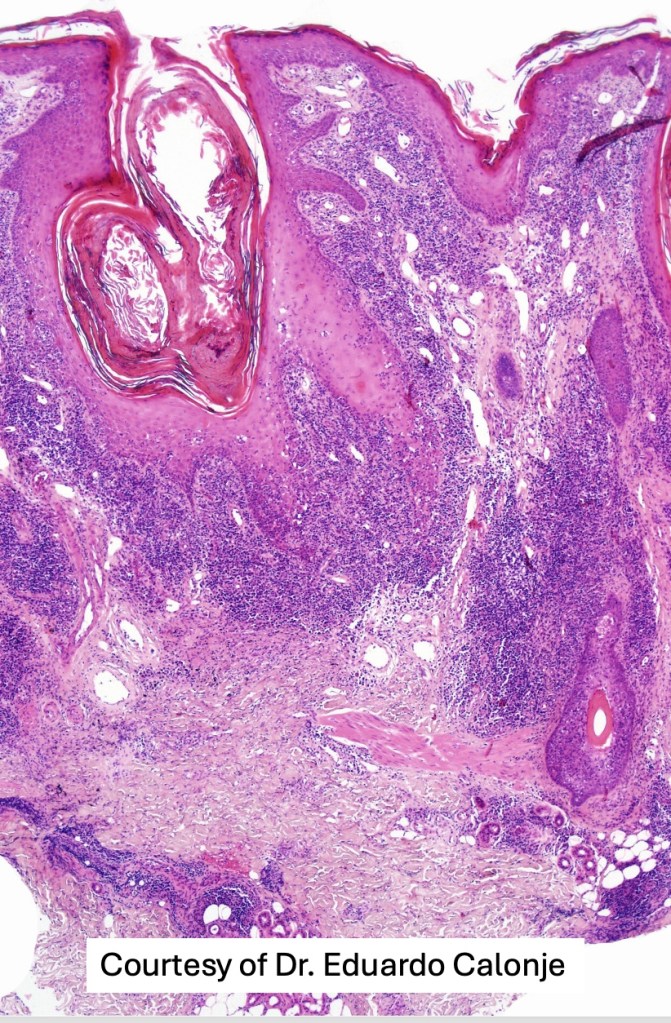

Histological features

•Epidermal involvement often absent

•Follicular infiltration by atypical lymphocytes & Sézary cells

•+/- mucinosis

•+/- syringotropic lesions

•+/- basaloid follicular hyperplasia

•Eosinophils sometimes conspicuous (eosinophilic folliculitis-like appearance)

•Granulomatous inflammation secondary to follicular destruction

•Large cell transformation occasionally present